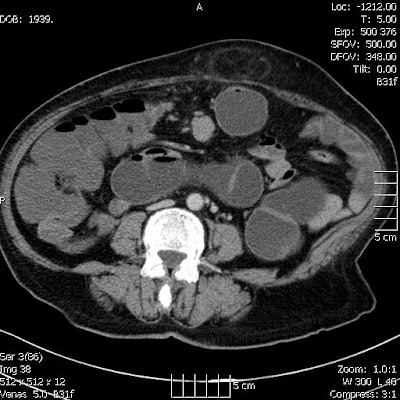

Megnagyobbodott, intenzíven halmozó mesenterialis nyirokcsomó a középvonalban

A vastagbelek vízzel töltve (hydro-colo CT készült, mert a colonoscopia nem volt végig kivitelezhető)